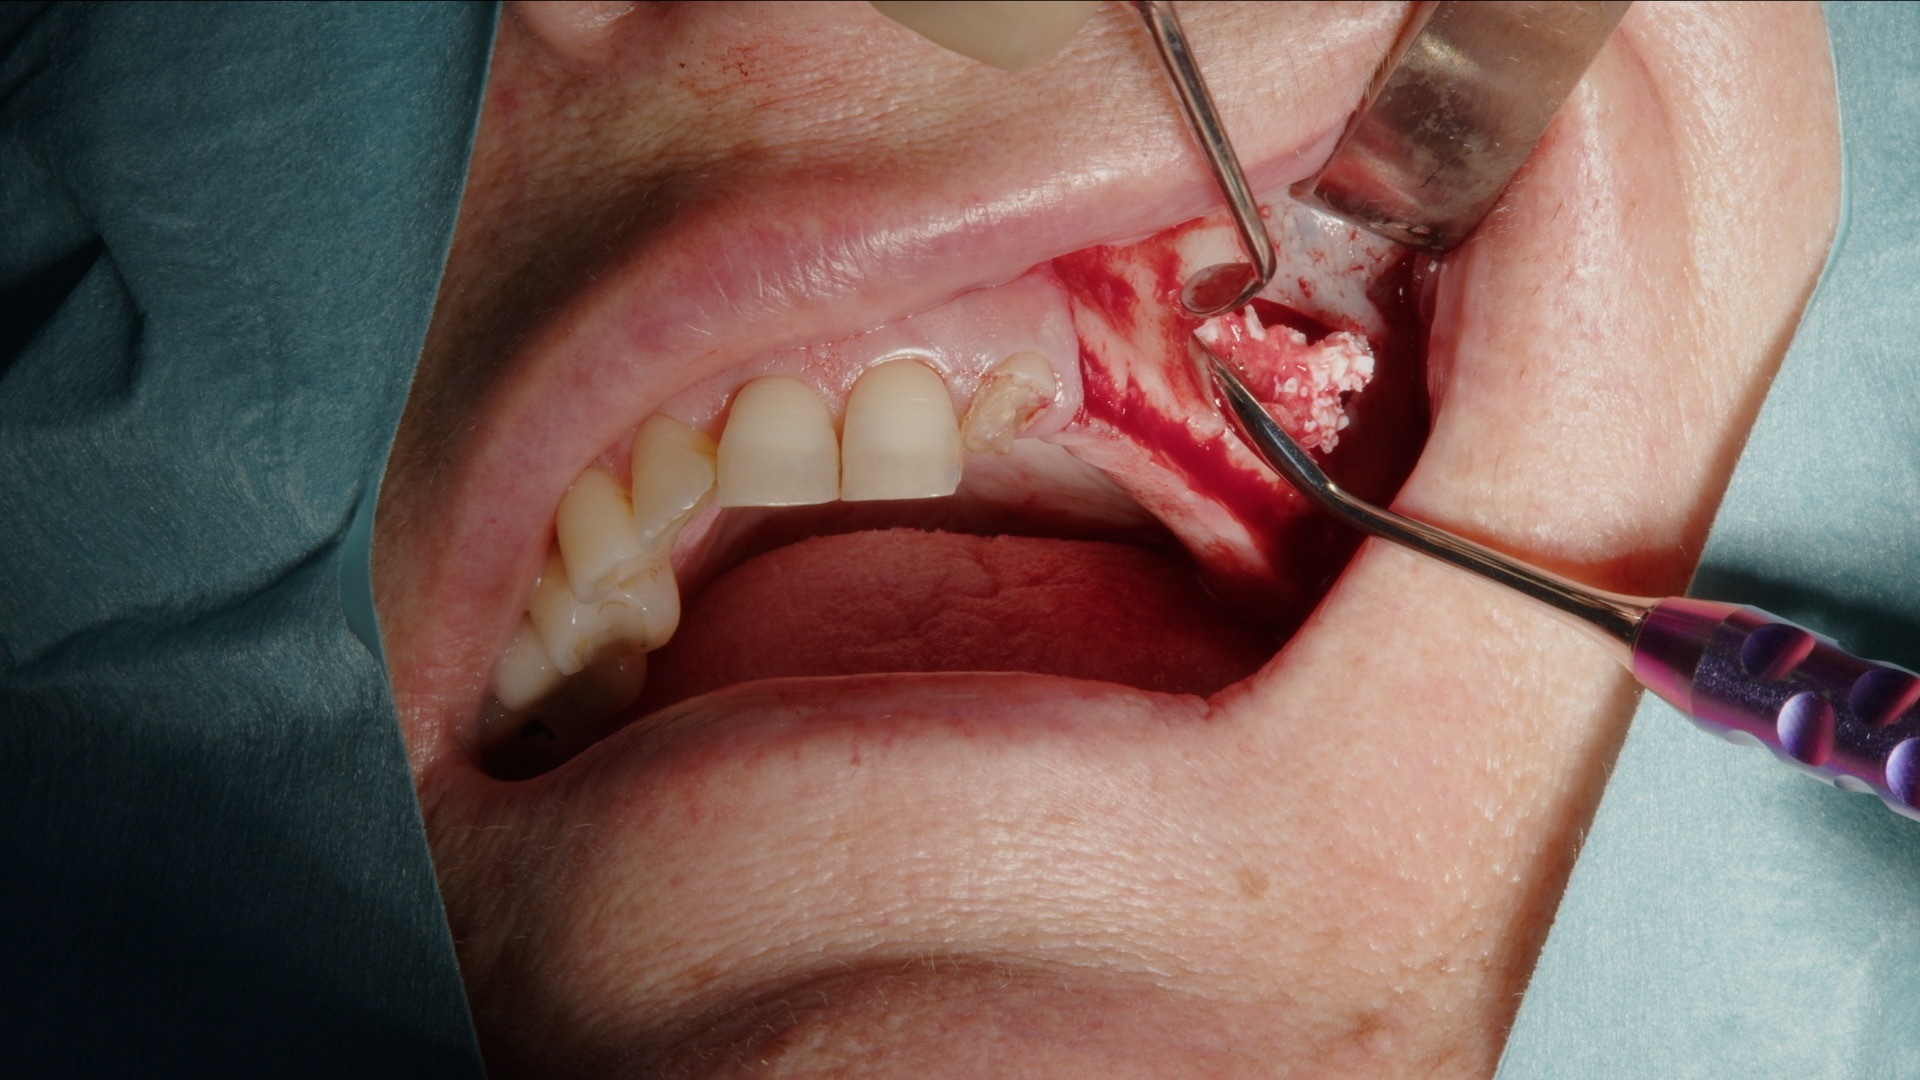

5. Ifyllnad med blandning av Geistlich Bio-Oss och autologt ben.

6. Fullständigt augmenterat sinusutrymme.

Autologt ben samlas in med Safescraper direkt från operationsområdet. Metoden är minimalt invasiv och ger vitalt benmaterial med hög biologisk potential. Det autologa benet blandas därefter med Gesitlich Bio-Oss för att skapa en stabil graftmassa med både osteokonduktiva och osteoinduktiva egenskaper.

Den färdiga blandningen placeras systematiskt i det skapade sinusutrymmet tills önskad volym uppnåtts. Kombinationen ger god vaskularisering, långsiktig volymstabilitet och förutsägbar benbildning.